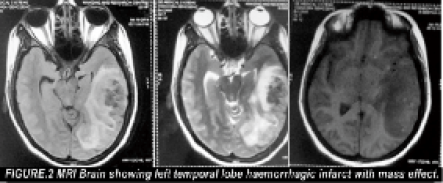

A young unmarried female presented with history of high grade fever of two days duration associated with head ache, vomiting, reeling sensation followed by delirium and seizures after roaming in a very hot summer day. Before getting admitted in the hospital she was treated with cold and wet blankets, intravenous fluids and antipyretics for one day . There was no history of any significant illness. She was not on any medication. On examination, patient was afebrile, drowsy and incoherent. Headache and vomiting are present. There were no signs of meningeal irritation or focal neurological deficits. Papilloedema was present. Her blood sugar, renal and liver function tests and electrolytes were within normal limits. Pregnancy test was negative and urine examination was normal. Computerised Tomogram of brain [Figure: 1] revealed hemorrhage in left temporal region associated with edema. Magnetic resonance scan of brain [Figure:2&3] showed hemorrhagic infarct in the left temporal region and thrombus in the left transverse and sigmoid sinus. Her connective tissue profile was normal (Antiphospholipid antibodies, Antinuclear antibodies, Anti ds-DNA were negative and, Protein C, Protein S, AntiThrombin III and Homocysteine were within normal limits).

- MRI Brain showing haemorrhagic infarct with mass effect in the left temporal lobe.